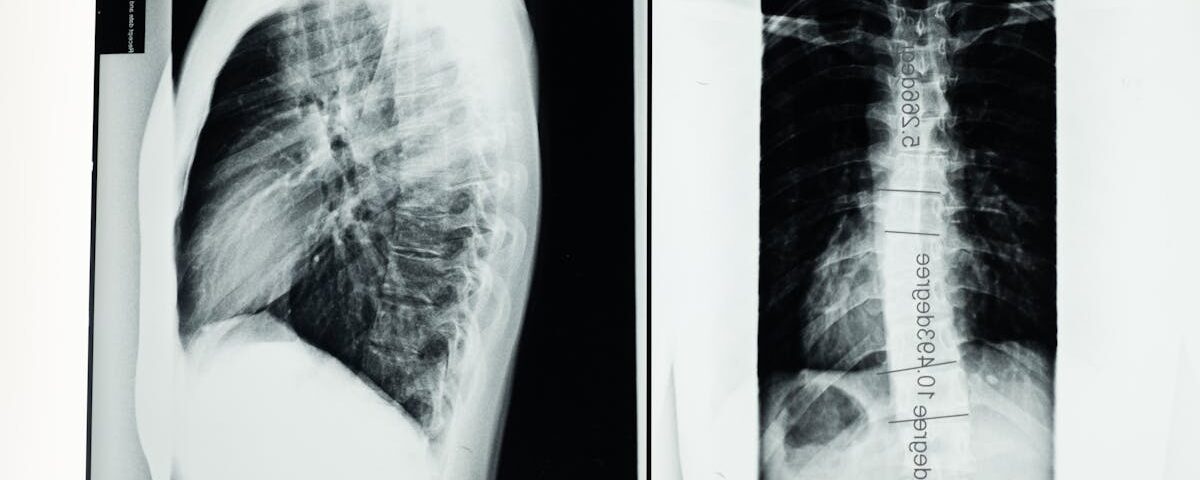

Avant de commencer un traitement de décompression vertébrale, il est crucial de réaliser une consultation approfondie. Cela inclut :

Un examen physique détaillé

Des bilans d’imagerie comme des radiographies ou IRM

La fourniture d’un historique médical complet